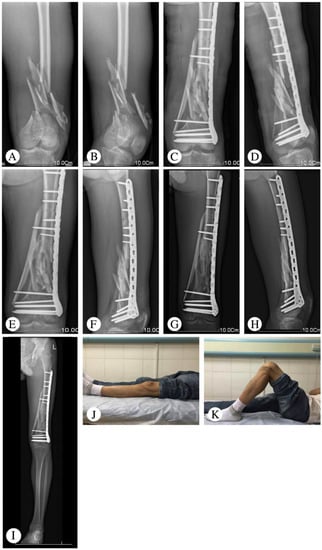

One patient had a deep infection five days after the operation and underwent a secondary surgery (implant removal and external fixation). There were two patients who had minor surgical complications, including one superficial wound infection and one partial wound dehiscence. After debridement and suturing, both patients’ complications were resolved. One patient with nonunion required bone grafting without hardware exchange. Post-traumatic arthritis was seen in one patient at the final follow-up, which was based on the radiologic assessment (Table 2). Typical cases are shown in Figure 1 (Patient 2), Figure 2 (Patient 5), and Figure 3 (Patient 10).

Figure 1. Representative images of Patient 2 (61-year-old male patient with a type A3 fracture that had been initially treated with dynamic condylar screws). (A,B) Implant breakage was observed seven months after surgery. (C,D) X-ray at 5 months after operation. Bone union was observed. (E,F) Follow-up X-ray at 36 months. (G,H) Follow-up X-ray at 60 months. (I,J) Follow-up X-ray at 73 months.

The main reasons for implant failure are primarily due to the following problems: (1) high bending stress exerted on the laterally placed plates in the presence of marked cortical defects and (2) locking plates are usually implanted using the minimally invasive percutaneous plate osteosynthesis (MIPPO) technique. Since the MIPPO technique is relatively short range and intraoperative fluoroscopy has a limited range, there is a high incidence (approximately 30%) of axial malalignment after surgery. Axial malalignment results in increased load on the plate, which can cause implant failure. Here, implant failure was found in two patients over the age of 60 who had been initially treated with a single-side plate and screws, followed by additional operations as needed. The current treatment approach for implant failure features scar tissue removal and large amounts of autologous iliac bone grafts, as well as implant replacement. Bilateral autologous iliac bone grafts have often been applied to repair cortical defects, which can increase surgical trauma and the chance of infection. Furthermore, the stability immediately following the structural allograft cannot support early postoperative functional exercise, which is important for recovery. Therefore, we performed a medial implant of the cortical bone plate allograft integrated with a lateral LISS plate for the two patients with implant failures. Patient 2 was a 61-year-old male patient with a type A3 fracture that had been initially treated using dynamic condylar screws. The implant failure was observed seven months following surgery and required reoperation. After treatment with a cortical bone plate allograft combined with LISS plate fixation, bone union was observed five months later (Figure 1).